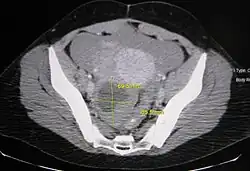

Imagerie

En échographie pelvienne, le kyste est visualisé par une image ronde, vide d'échos. Il peut exister des septums, qui ne sont pas évocateurs d'un cancer[5].

L’irrégularité de la paroi du kyste est plus suspecte, nécessitant une surveillance rapprochée ou une exerèse chirurgicale[6].